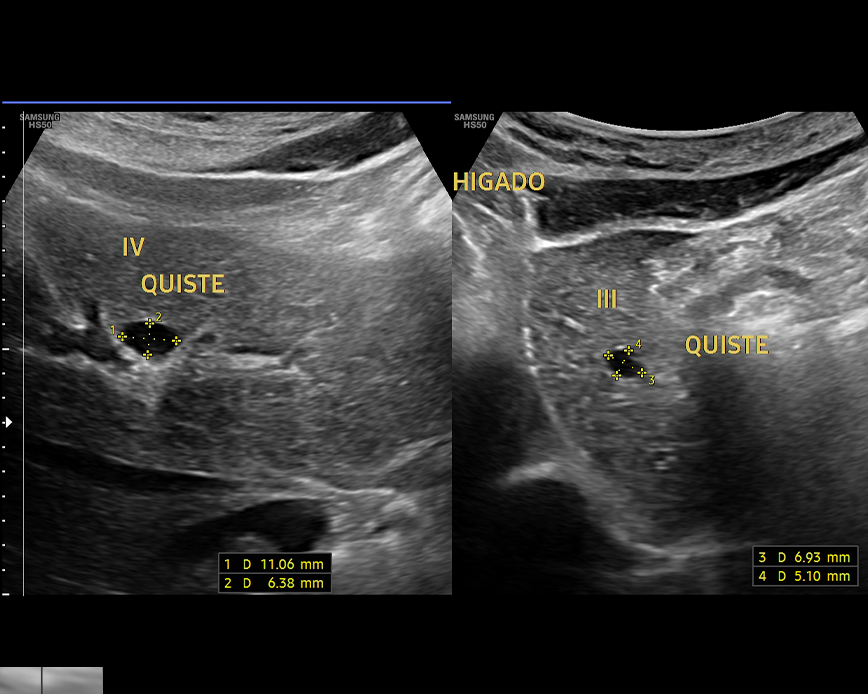

- Diagnostico de enfermedades hepáticas